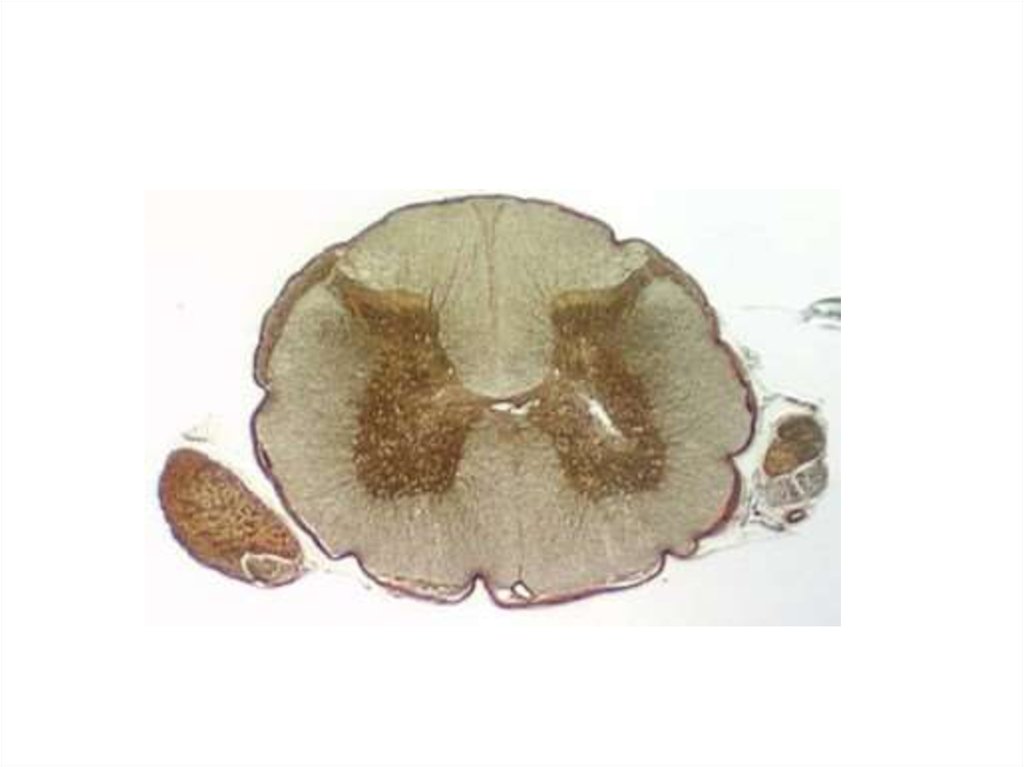

Спинной мозг и ствол мозга

Спинной мозг. Строение спинного мозга и функции

Спинной мозг. Строение спинного мозга

Спинной мозг. Ствол мозга

Спинной мозг

Спинной мозг. Оболочки головного и спинного мозга. Проводящие пути

Спинной мозг. Строение

Спиной мозг